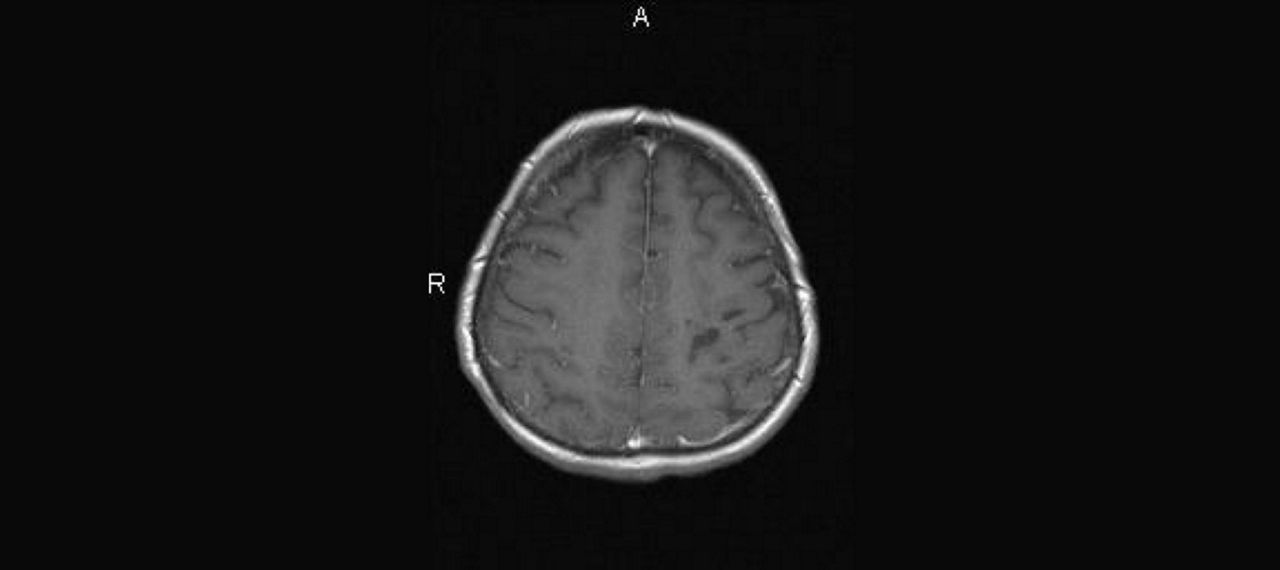

Abb. 4: Nach 2 Monaten

Abb.6: 4 Monate nach Vorstellung: Zunahme der flächigen Marklage-Läsionen und der zystischen Defekte

AUFLÖSUNG FALL 1

Diagnose: NMOSD

AQP4-IgG: stark positiv

Conclusio: Einige MS-Therapien, u. a. Natalizumab, können NMOSD verschlechtern, schlechter Langzeitverlauf